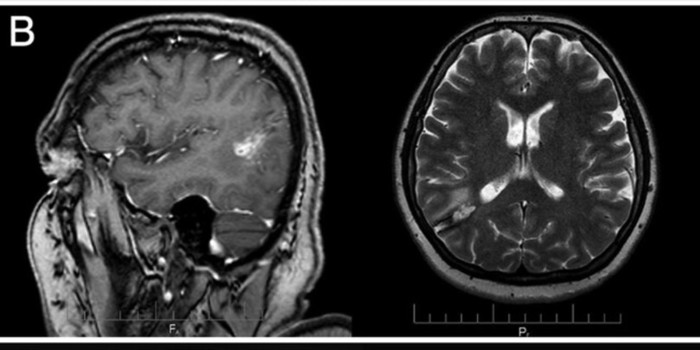

საქართველოში ქალის ტვინიდან 15-სანტიმეტრიანი ცოცხალი პარაზიტი Taenia solium, ანუ ღორის სოლიტერი, ამოიყვანეს. ქართველმა ქირურგებმა ეს შემთხვევა დეტალურად აღწერეს, მათი ნაშრომი კი ახლახან რეფერირებად გამოცემაში Journal of Neurosurgery გამოქვეყნდა.

ონკოლოგიური ისტორიის მქონე 54 წლის ქალი ქირურგებთან ტვინის სიმსივნის დიაგნოზით მივიდა. ამოკვეთის მცდელობისას ექიმებმა ტვინში 15-სანტიმეტრიანი ცოცხალი ჭია შენიშნეს.

ამოყვანილი ჭია შემდგომში პარაზიტოლოგიის ინსტიტუტმა შეისწავლა. დადასტურდა, რომ ქალს ტვინში მართლაც ზრდასრული თასმისებური ჭია, T. solium, ჰყავდა. ტვინის ქსოვილის მიკროსკოპული კვლევით თასმისებური ჭიის კვერცხებიც შენიშნეს, რომლებიც განვითარების სხვადასხვა სტადიაზე იყო; მათ სპეციფიკური სქელი, ზოლიანი გარსები ჰქონდა.

ოპერაციიდან რამდენიმე თვის განმავლობაში ქირურგები შემთხვევის შესწავლასა და აღწერაზე მუშაობდნენ. ნაშრომმა რეცენზირება გაიარა და რეფერირებად სამეცნიერო ჟურნალში გამოქვეყნდა. გამოდის, სამეცნიერო ლიტერატურაში ეს პირველი დადასტურებული შემთხვევაა, როცა ადამიანის თავის ტვინში ზრდასრული ღორის სოლიტერი დაფიქსირდა.

წაიკითხეთ ვრცლად: ადამიანის ტვინში ზრდასრული ღორის სოლიტერი პირველად დაფიქსირდა და ეს საქართველოში მოხდა